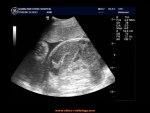

1、B超:以超音波可看到胎頭在母親子宮之側方。